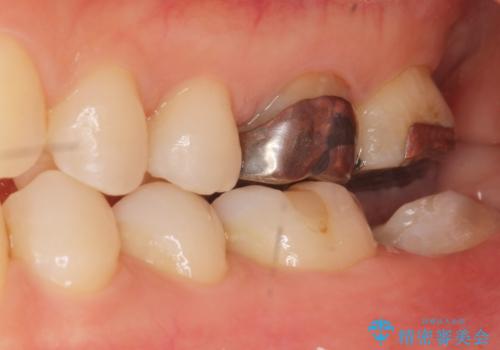

割れている奥歯を抜去後左上の機能していない親知らずを移植し、生着したのち根管治療・補綴を行いました。

インプラントや義歯を用いることなく咬合を回復することができ、喜んで頂けました。

治療期間も抜歯後3ヶ月以内かつ少ない来院回数(初診含めて6回)で治療を終えることができ、ご満足頂けました。

被せ物の種類:メタルボンドクラウン エコノミー フルベイク